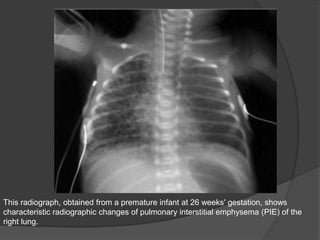

PULMONARY INTERSTITIAL EMPHYSEMA

Definitions

• Abnormal location of pulmonary air within the interstitium and lymphatics; usually

secondary to barotrauma. This collection develops as a result of alveolar and terminal

bronchiolar rupture. It is more frequent in premature infants who require mechanical

ventilation for severe lung disease.

Radiography

o Bubble-like or linear lucencies within the lung

o Lucencies typically uniform in size

o Often radiate from hilum

o May be focal (one lobe) or diffuse and bilateral

This radiograph, obtained from a premature infant at 26 weeks' gestation, shows

characteristic radiographic changes of pulmonary interstitial emphysema (PIE) of the

right lung.